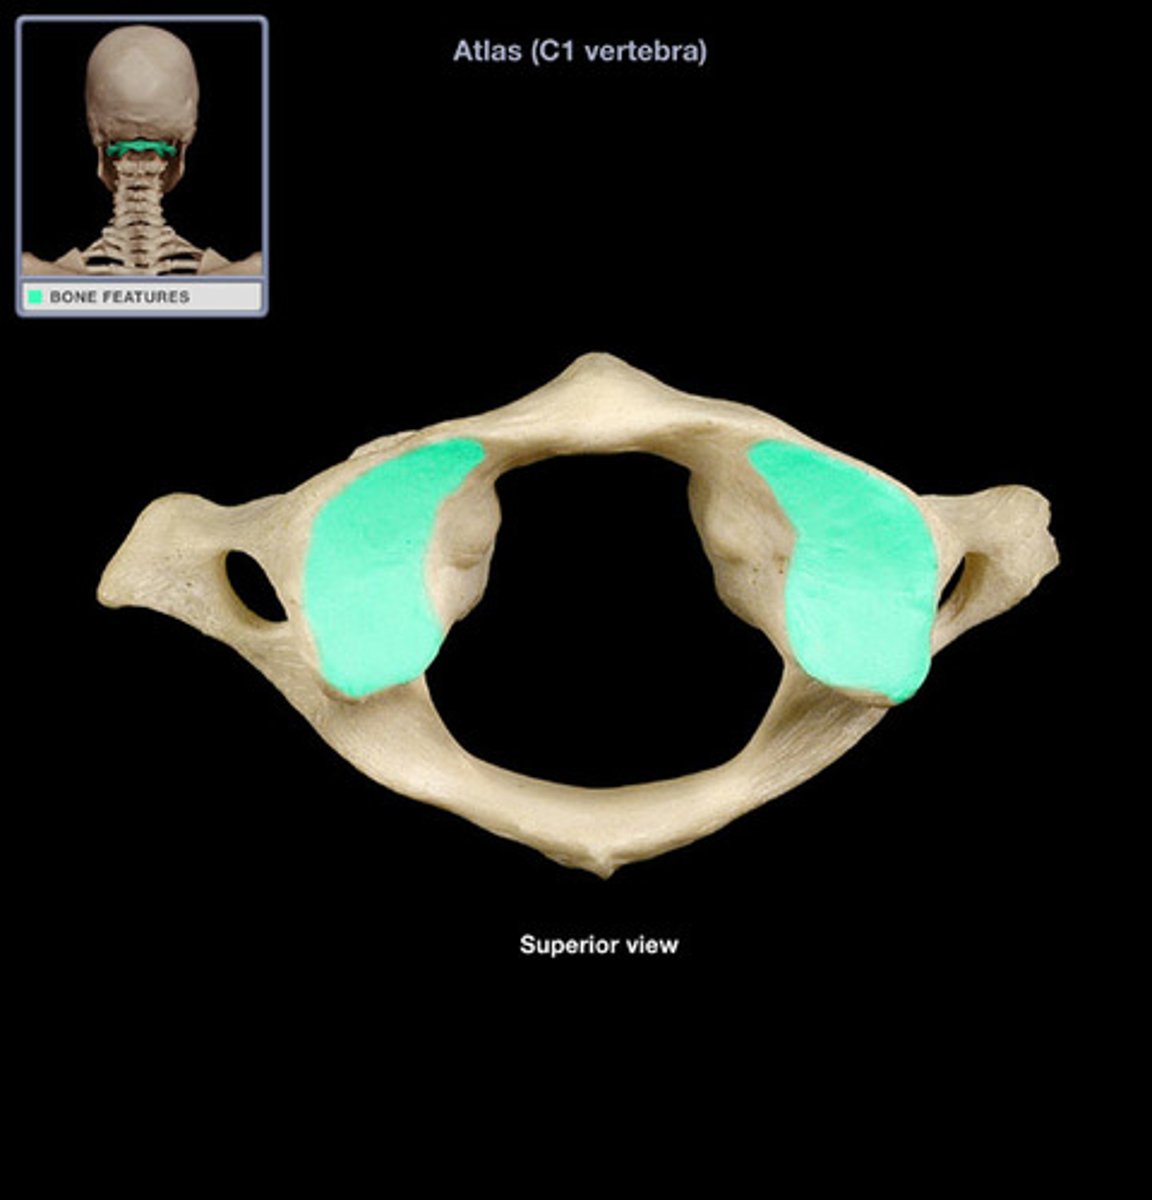

superior articular facet of occipital condyle

atlas C1

what vertebra is considered the atlas

hold head up

what is the purpose of C1

what vertebra is visually a flat bone